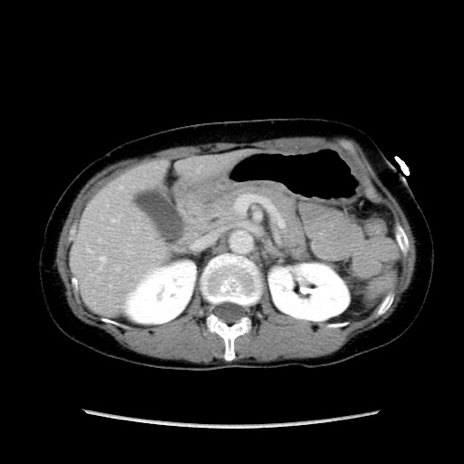

冠状断像

【症例】40歳代 女性

【主訴】上腹部痛、嘔気・嘔吐

【現病歴】約9時間前頃から急に上腹部痛、嘔気、嘔吐が出現。改善しないため救急要請。

【既往歴】子宮頚癌(広汎子宮全摘術、放射線療法)、腸閉塞

【身体所見】腹部:平坦、軟、腸雑音亢進、上腹部を中心に腹部全体に圧痛あり。

【データ】WBC 8400、CRP 0.03